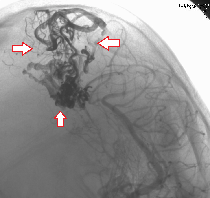

(下図)けいれんで発症した大型の脳動静脈奇形を、液体塞栓物質Onyxを用いて塞栓しました。ほぼ完全な閉塞が得られています。

脳動静脈奇形

塞栓術後